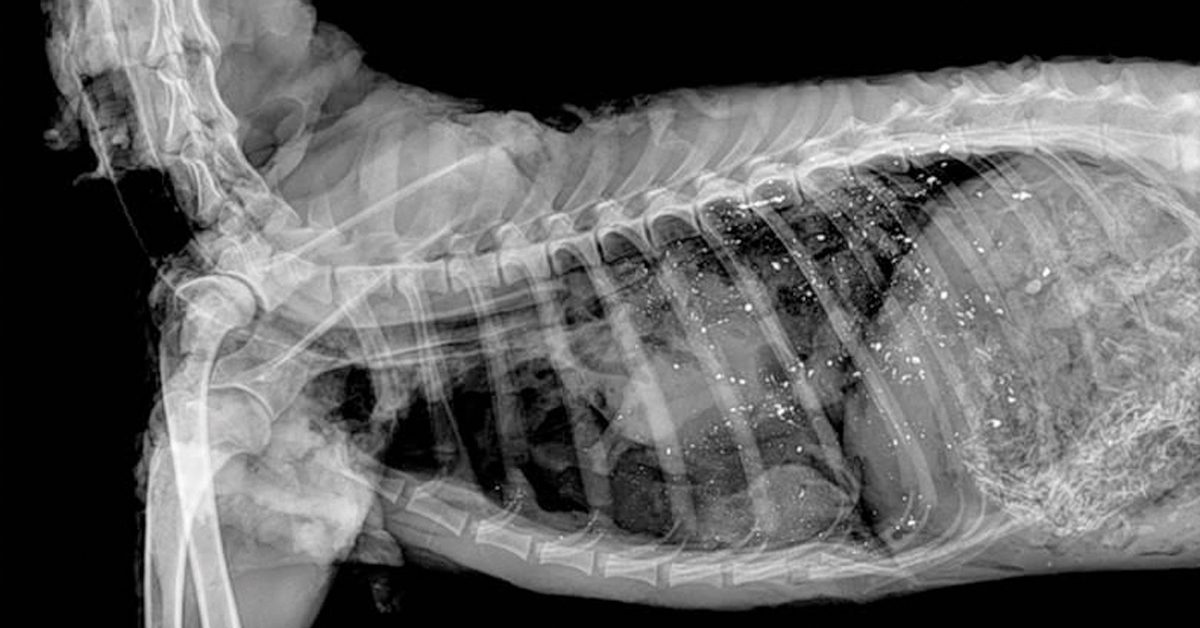

This deer was shot with a lead bullet. The bright white spots scattered throughout its body are fragments of lead from that bullet. These fragments can be eaten by scavengers, such as eagles, when they feed upon a gut pile or carcass left out in the field. © USGS.gov

The soft nature of metallic lead not only allows for bullet expansion, but it allows the bullet to come apart and fragment when it hits meat and bone. It is not hard to find X-ray photos on the Internet and hunting regulations showing the scatter of lead fragments in a carcass. Some pictures represent worst-case scenarios from a high-velocity, lightweight bullet that impacted solid bone. Nonetheless, lead bullets do fragment. Recent research shows even skeptical hunters that there is more lead in our venison (and farther from the wound channel) than we thought. With a well-placed shot in the lungs, bullet fragments in the four quarters and backstraps should be minimal. Most of the contamination comes from the scraps of meat taken from the area near the wound channel, which typically end up in the “grind pile” for burger.

The Minnesota Department of Natural Resources experimentally shot 80 carcasses and evaluated the presence of lead. High-velocity ballistic-tip bullets left an average of 141 fragments, an average of 11 inches from the wound channel. Soft-core and bonded bullets fragmented less and left 80-86 fragments 9-11 inches from the wound channel. Some fragments were too small to see with anything but an X-ray image.